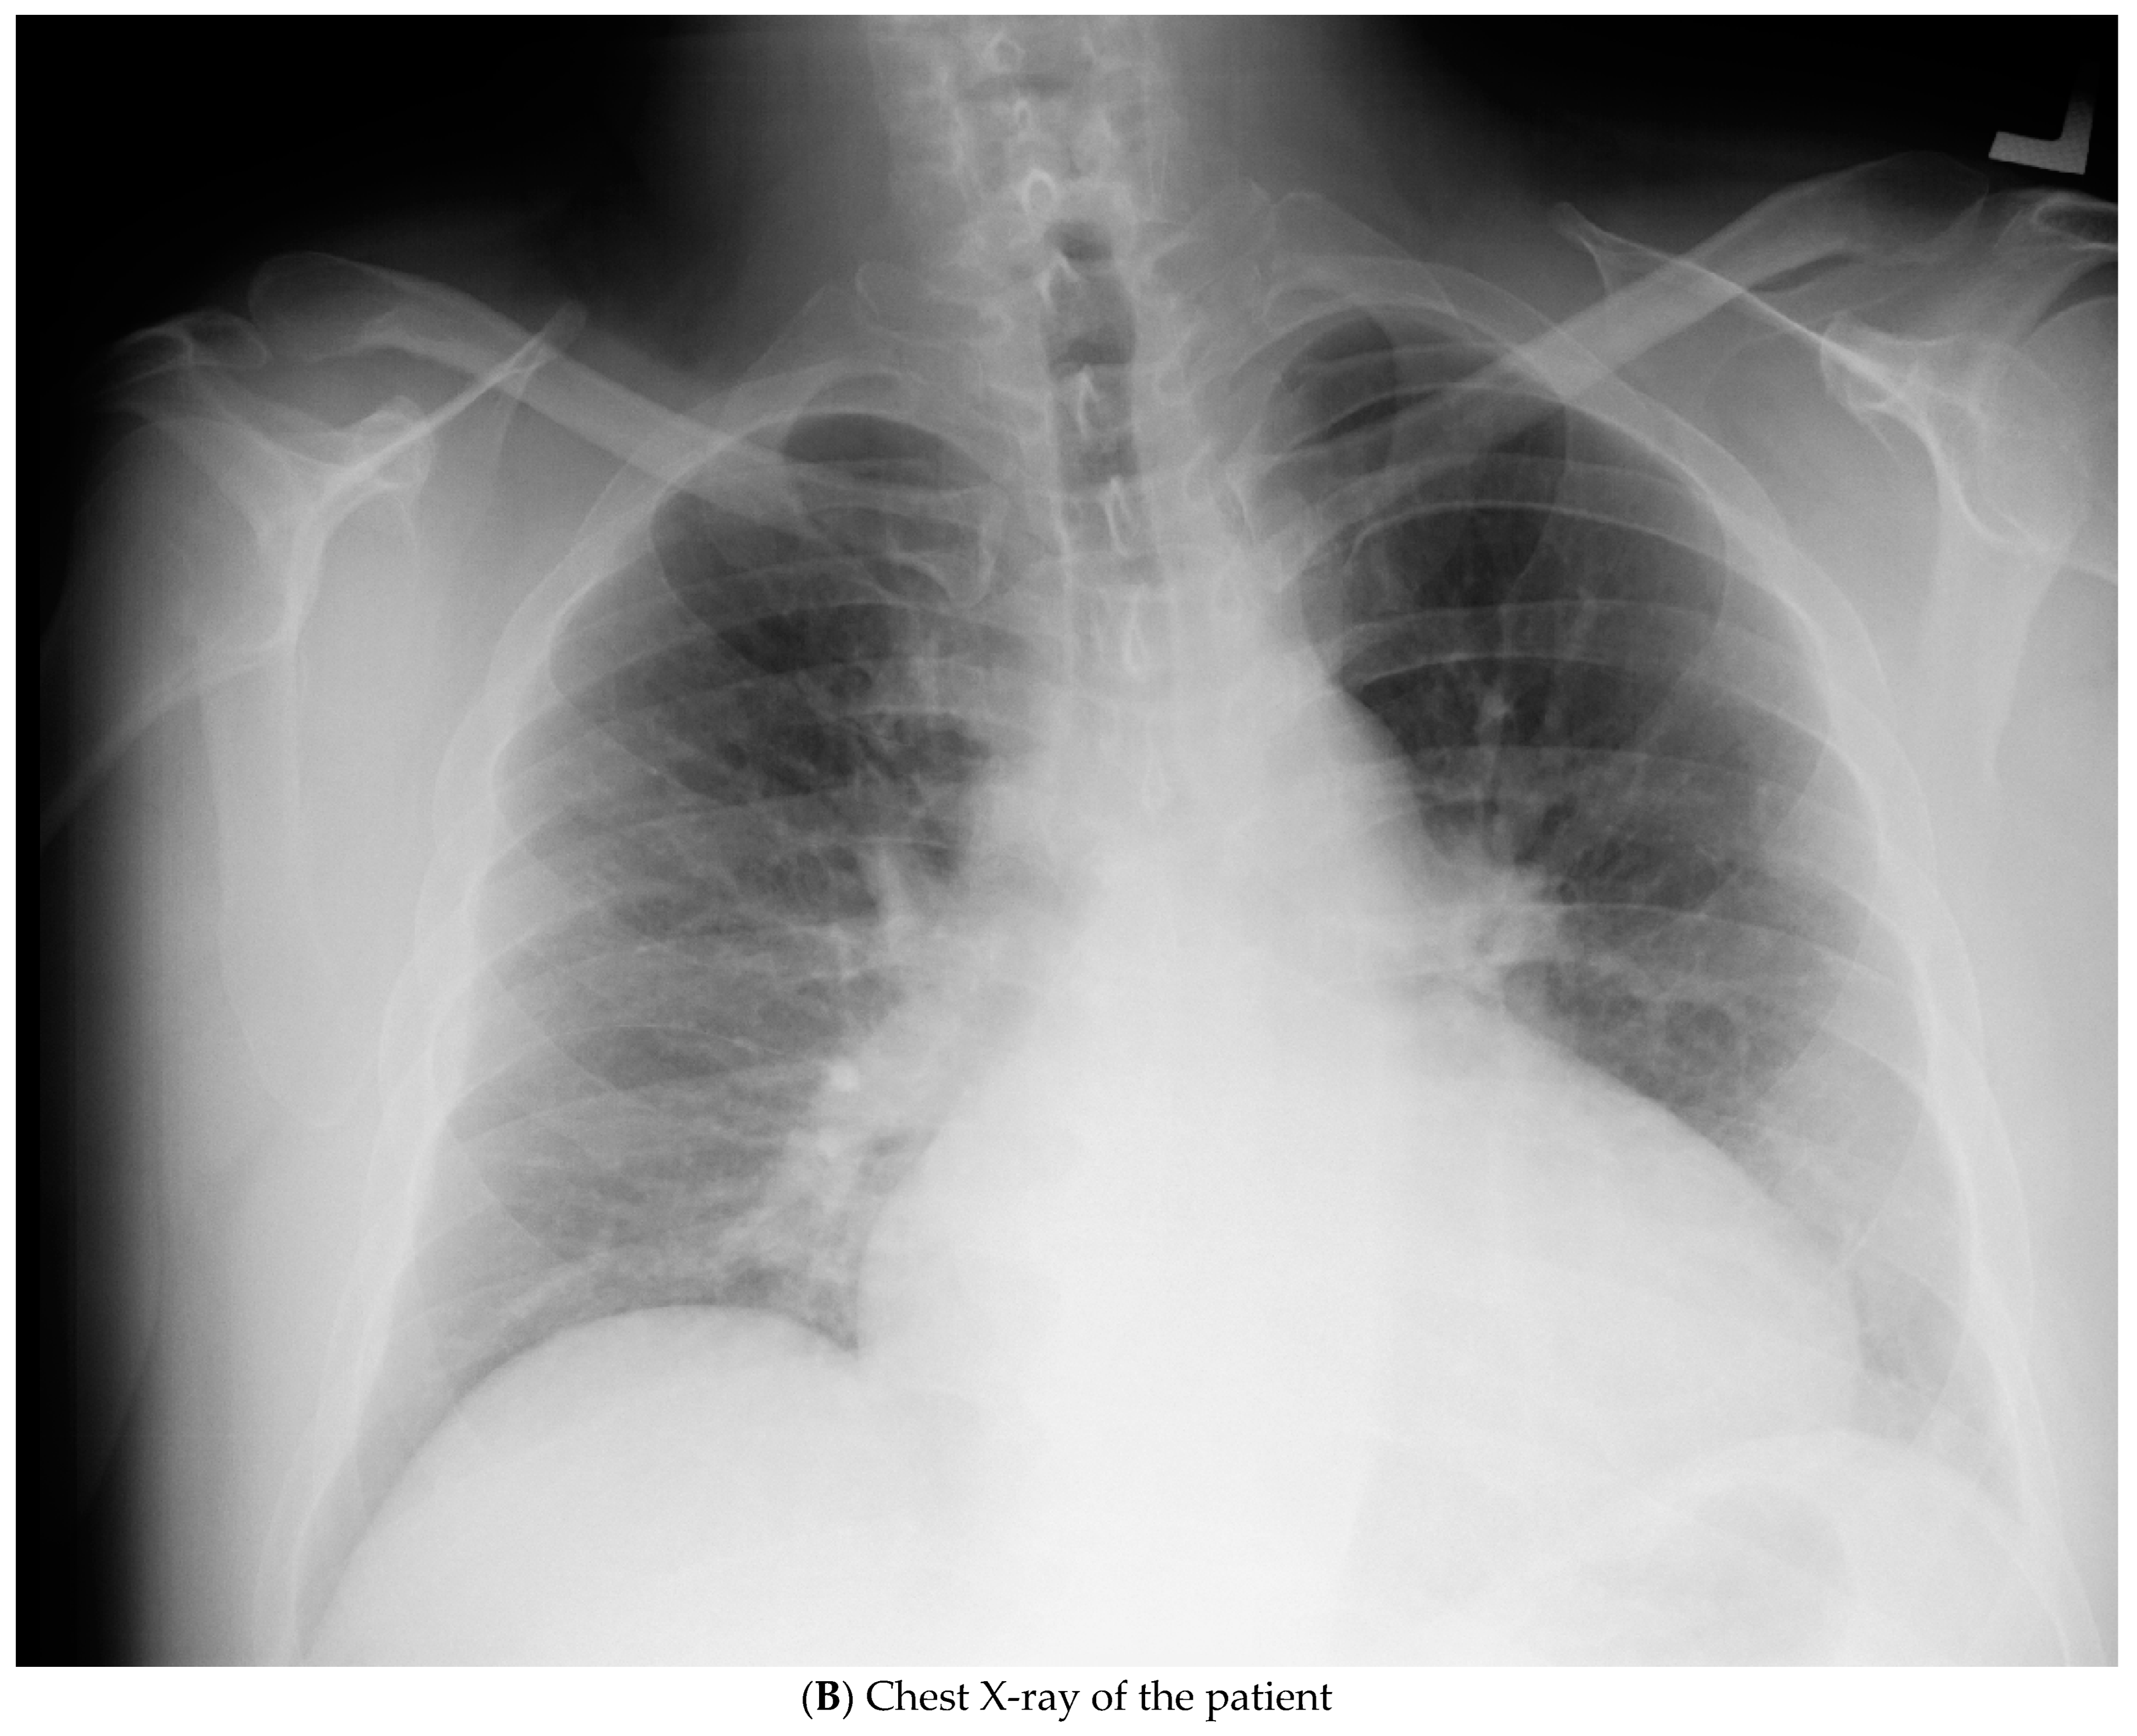

| 2016, age 41 | Ischemic stroke | Risk factor: Arterial hypertension, grade I; Heart enlargement described on chest X-ray; No specific follow-up recommended.  | Clopidogrel 75 mg Piracetam 2400 mg Irbesartan 75 mg  |

| March 2021, age 45 | First episode of decompensated heart failure, NYHA III-IV class; A new episode of persistent AF, duration longer than two months | Management of failure according to guidelines; TEE not performed due to INR not being in target; Asymmetric left ventricular hypertrophy and reduced ejection fraction noted; Further diagnostic work-up recommended—cardiac magnetic resonance (CMR) and genetic testing; Test for Anderson–Fabry disease—negative; CMR study positive for cardiomyopathy with diffuse fibrosis, possibly hypertrophic or infiltrative.  | At admission: Amiodarone 400 mg; Torasemide 20 mg; Irbesartan 75 mg; Acenocoumarol; At discharge: Torasemide 50 mg; Spironolactone 50 mg; Acenocoumarol; Bisoprolol 5 mg; Sacubitril/valsartan 2 × 24/26 mg; Allopurinol 150 mg; Dapagliflozin 10 mg  |